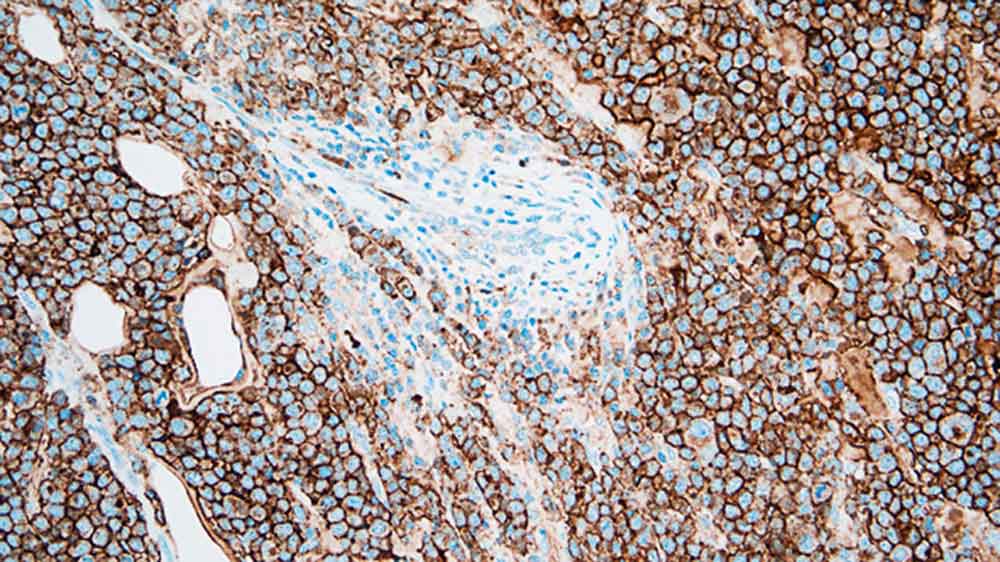

Plasmacytoma: immunohistochemical staining for CD138. Note the intense membrane staining of tumor cells. CD138: clone MI15

A molécula CD138 é uma glicoproteína de sulfato de heparina transmembranária expressada em estágios distintos de diferenciação em células linfáticas normais tais como células pré-B, células B imaturas e células de plasma produtoras de lg assim como sendo expressa no epitélio estratificado e simples. A perda de expressão CD138 a partir de células atípicas é relatada ser um evento prematuro durante a carcinogênese cervical enquanto a expressão do antígeno CD138 mostra uma associação próxima com a morfologia e diferenciação epitelial preservada, entretanto, a principal utilidade da CD138 como um marcador na imuno-histoquímica é a quantificação das células do plasma.